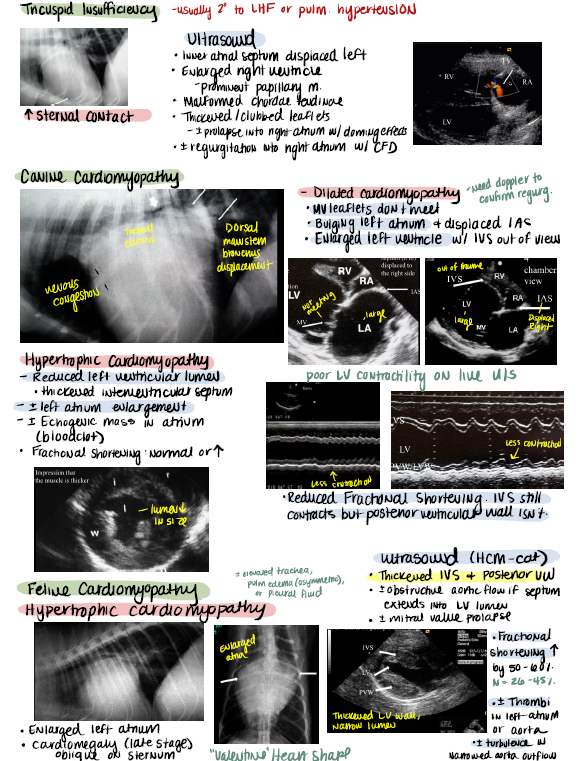

Comprehensive large animals notes for NAVLE Prep and NAVLE exam